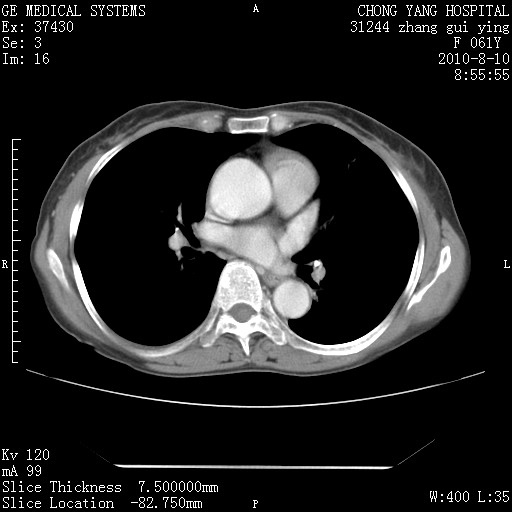

标题: CT28314:F61Y胸部增强,发热咳嗽一周入院,后面的为一周前平

1、支持考虑右侧中央型肺癌伴右肺中叶节段性不张及下叶支气管黏液痰栓    2、左肺上叶舌段感染。

支持3楼意见,还要考虑:纵隔及肺门淋巴结转移、右侧少量胸腔积液。

确切的说:1:右肺下叶中心型肺癌侵及中叶支气管并中叶不张,纵膈淋巴结转移。2:左肺舌叶炎症。3:右侧胸腔少量积液

块影平扫32hu,动静脉期62-70hu.

1:右肺下叶中心型肺癌侵及中叶支气管并中叶不张,纵膈淋巴结转移。2:左肺舌叶炎症。3:右侧胸腔少量积液。支持!

右肺下叶内基底段近膈不规则肿块,考虑右肺下叶周围型肺癌可能性大。

考虑右下肺肺癌,纵隔淋巴结转移i。